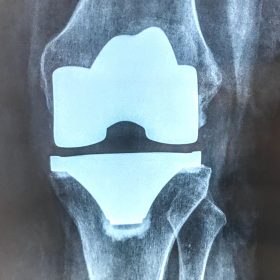

Σε αυτό το σημείο η Αρθροπλαστική Γονάτου αποτελεί μονόδρομο.